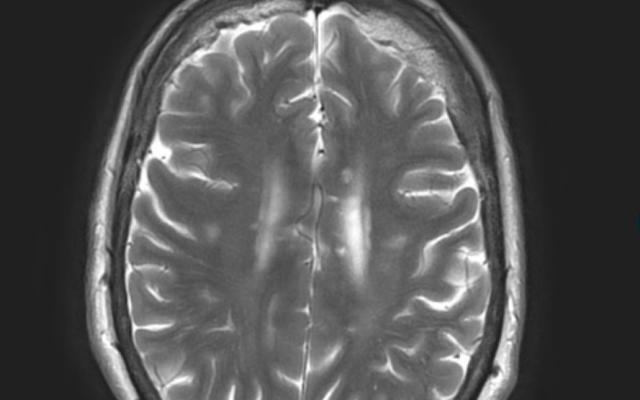

Heeft deze vrouw het syndroom van Susac?